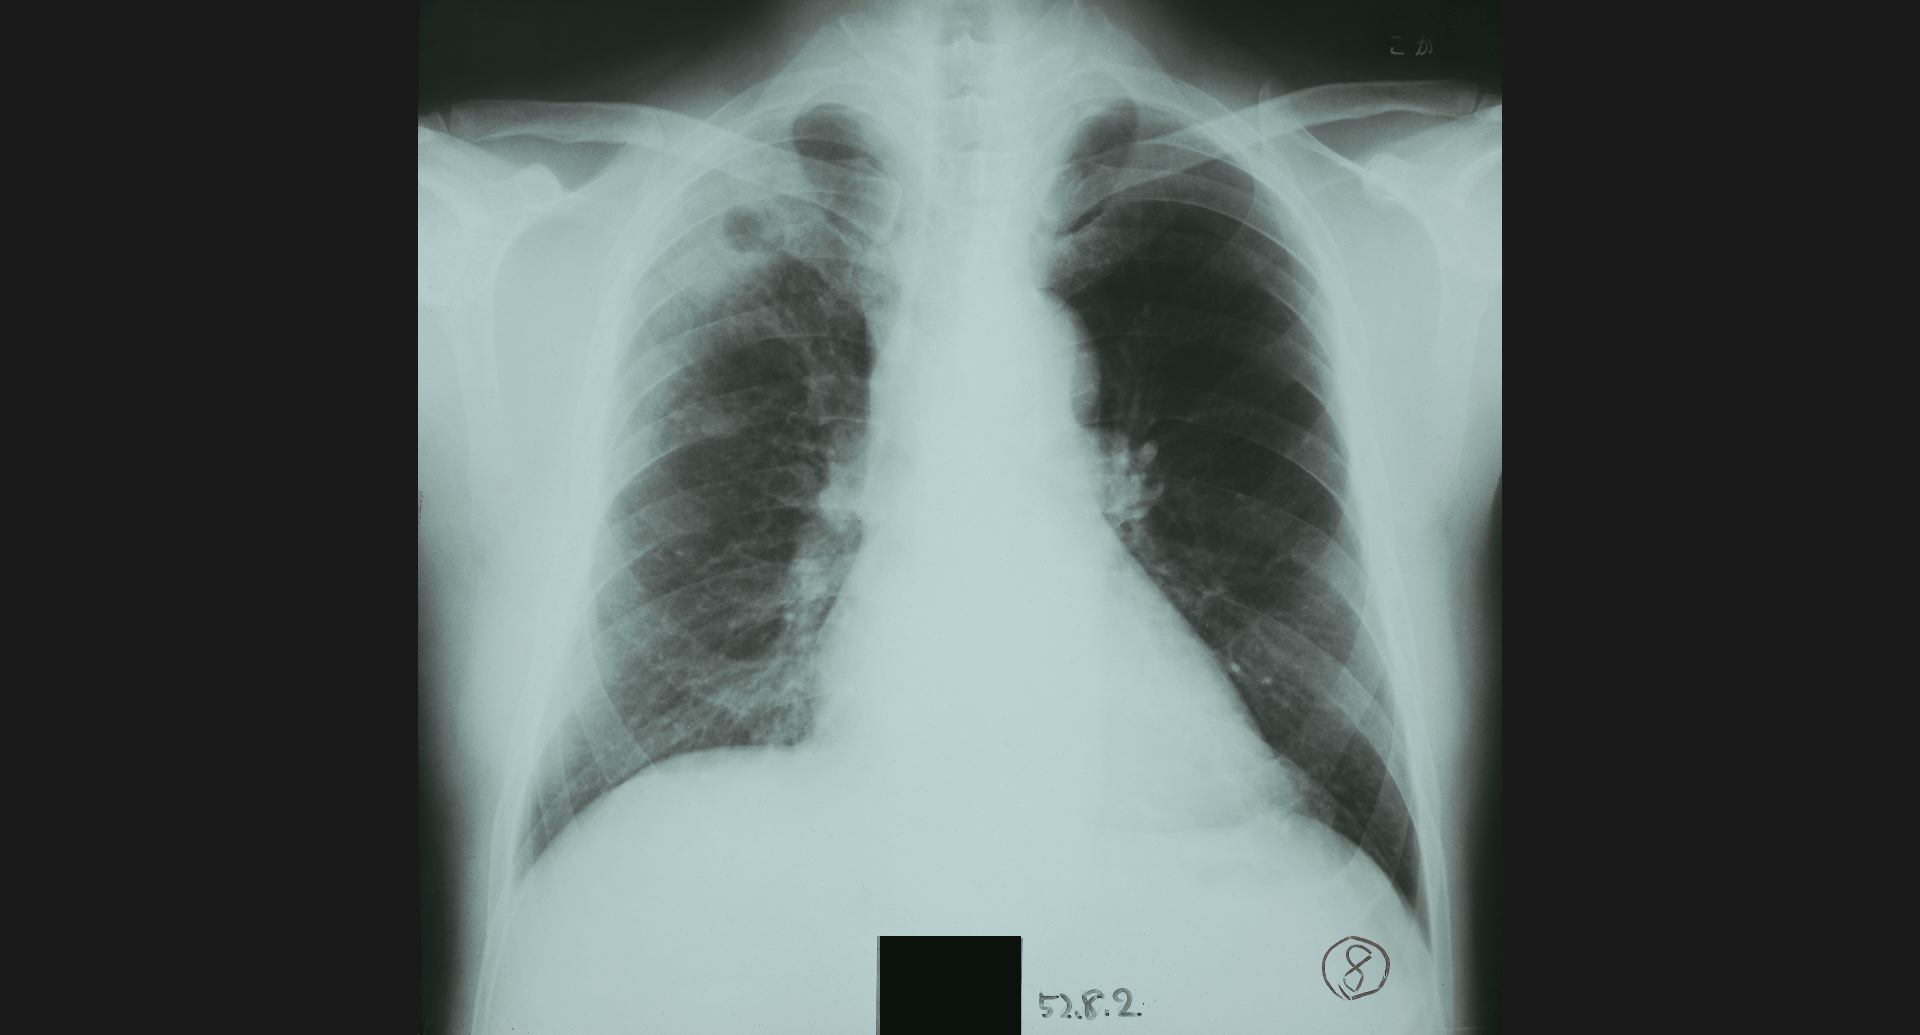

fig.2(104KB) :気胸

fig.3(105KB) :食道狭窄、肺炎

食道狭窄は、double aortic archによる。 肺炎は、造影の細かいところ。